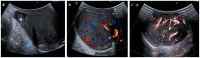

Pre- and post-pubertal testicular tumors are two distinct entities in terms of epidemiology, diagnosis and treatment. Most pre-pubertal tumors are benign; the most frequent are teratomas, and the most common malignant tumors are yolk-sac tumors. Post-pubertal tumors are similar to those found in adults and are more likely to be malignant. Imaging plays a pivotal role in the diagnosis, staging and follow-up. The appearance on ultrasonography (US) is especially helpful to differentiate benign lesions that could be candidates for testis-sparing surgery from malignant ones that require radical orchidectomy. Some specific imaging patterns are described for benign lesions: epidermoid cysts, mature cystic teratomas and Leydig-cell tumors. Benign tumors tend to be well-circumscribed, with decreased Doppler flow on US, but malignancy should be suspected when US shows an inhomogeneous, not-well-described lesion with internal blood flow. Imaging features should always be interpreted in combination with clinical and biological data including serum levels of tumor markers and even intra-operative frozen sections in case of conservative surgery to raise any concerns of malignity. This review provides an overview of imaging features of the most frequent testicular and para-testicular tumor types in children and the value of imaging in disease staging and monitoring children with testicular tumors or risk factors for testicular tumors.